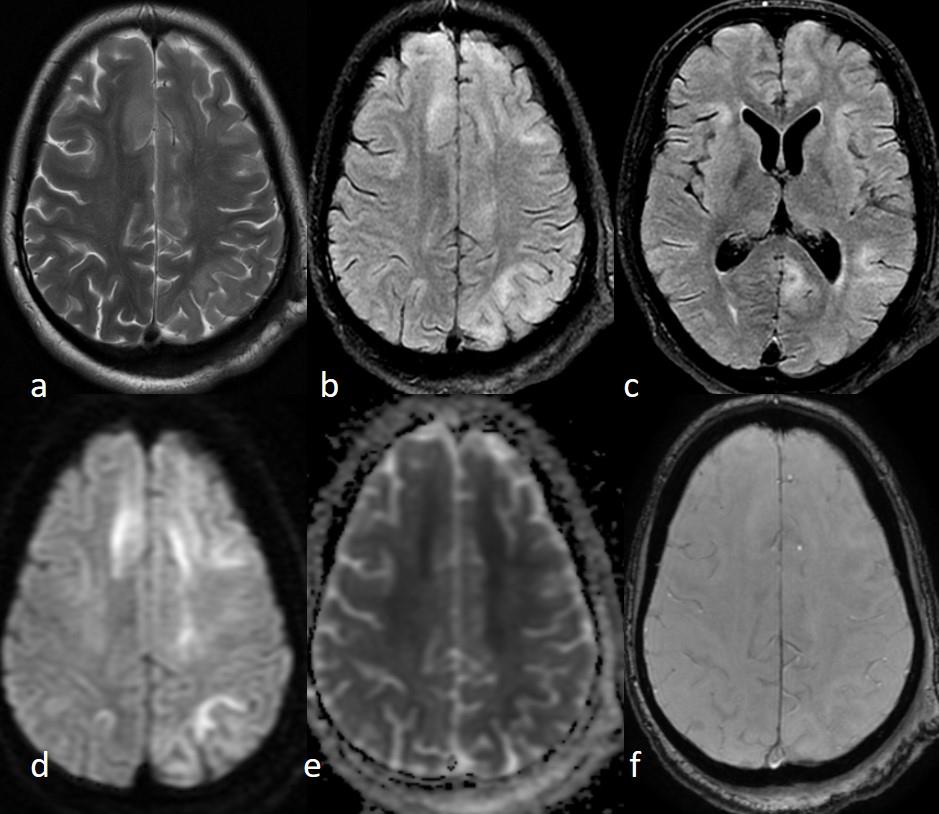

On investigation, CBC showed mild leukocytosis. The fever work-up which included peripheral blood smear to look for malarial parasites, rapid test for Dengue NS 1 antigen, serology for typhoid and paratyphoid causing organisms, blood cultures all of which were negative. The non-contrast enhanced CT scan (NCCT) head was normal. The initial Cerebrospinal fluid (CSF) analysis revealed mildly elevated protein (49.2 mg/dl) with normal cell count (2/mm3) and glucose concentration (67 mg/dl) and no growth on culture. Her CSF autoimmune panel was negative for Anti NMDA, AMPA1 and AMPA2, CASPR, LGI-1 and GABAB receptors. MRI Brain revealed patchy asymmetric confluent T2/FLAIR hyperintensities involving deep and subcortical white matter of bilateral frontal, left parietooccipital, temporal lobe, body and splenium of corpus callosum (Figure1). These findings were suggestive of subacute sclerosing panencephalitis (SSPE). On further workup of the CSF using Enzyme Immunoassay (EIA) confirmed raised anti measles antibody (CSF Ig G level= 298.46 U/ml) and total IgG (CSF total IgG= 22.09). The serology showed parallel results with a raised serum anti measles antibody (Serum IgG measles= 224.62 U/ml). The CSF/Serum quotient was elevated (3.23). The Electroencephalogram (EEG) done for the patient showed generalized background slowing in the deltatheta range. [Figure 2]

Figure 1:MRI Brain Axial T2weighted (a) and FLAIR (b and c) images

show bilateral, asymmetrical, multiple ill-defined hyperintense lesions

predominantly involving the subcortical and deep white matter. Axial

trace (d) and Apparent Diffusion Coefficient (ADC) (e) maps demonstrate

patchy diffusion restriction in some of the lesions. No foci of susceptibility are

seen on the Susceptibility weighted imaging (SWI) image (f).